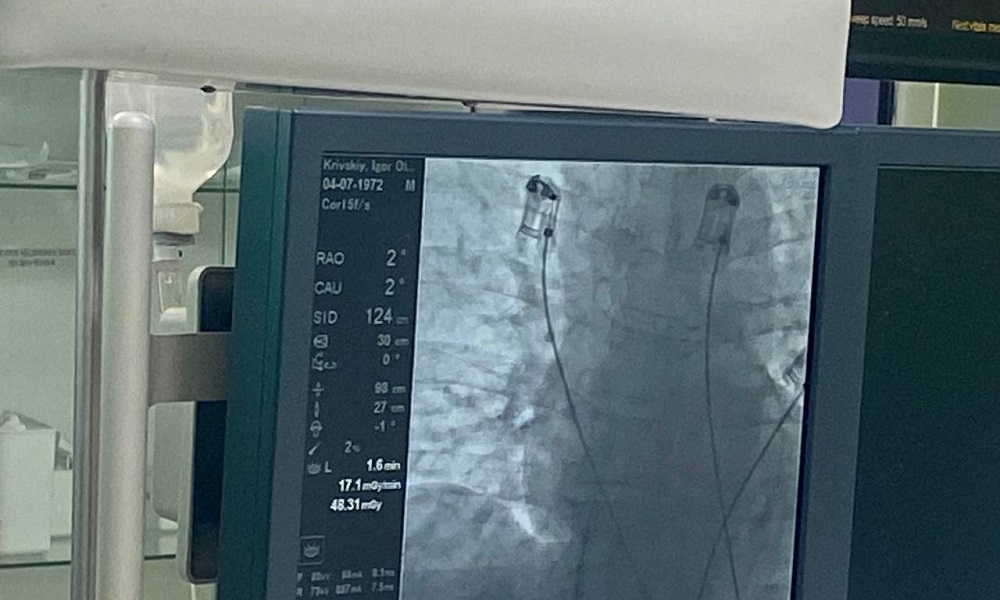

БСМП № 1 — первая из омских клиник, кто внедряет у себя методику хирургического лечения фибрилляции предсердий методом криоаблации. Нарушение ритма сердцебиения может привести к сердечной недостаточности, а в последствии — к инсульту. Газ оксида азота (температура до -80 градусов) охлаждает проблемный участок сердца, что позволяет ликвидировать клетки, провоцирующие аритмию.

Как рассказала заведующая отделением кардиологии РСЦ БСМП № 1 Ольга Швед, операция длится полтора часа. Пациенту не придётся долгое время употреблять таблетки. Реабилитация занимает 2 месяца, после — он ведёт обычный образ жизни. Данный метод сейчас активно внедряют в регионах, поскольку с каждым годом количество пациентов с таким диагнозом увеличивается. Как отметили в минздраве, в следующем году операцию будут проводить в рамках ОМС благодаря нацпроекту «Здравоохранение».